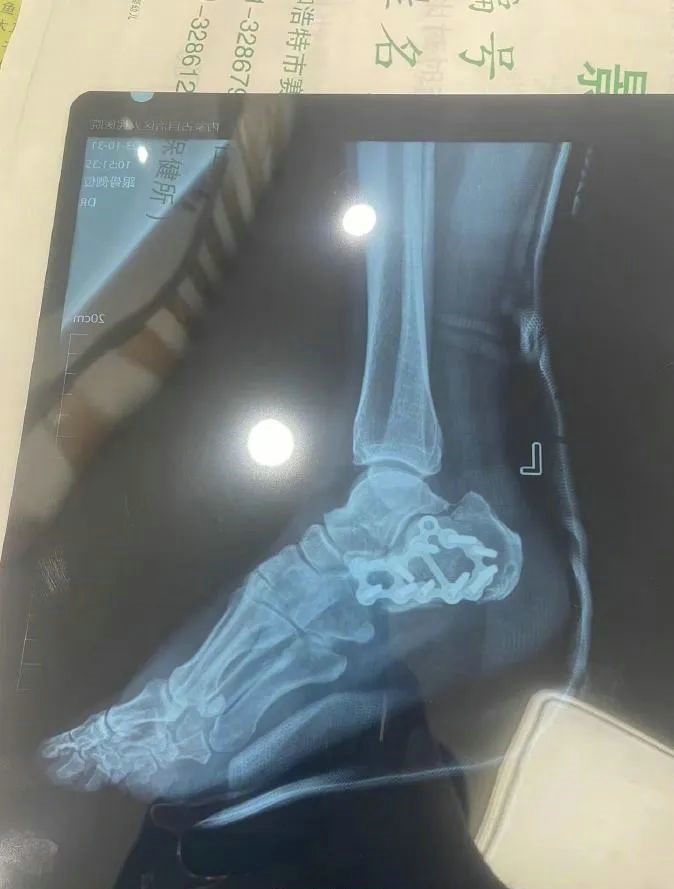

“那時候我剛工作了兩天,在第三天10月22日下午施工過程中從三層高的鐵架上摔了下來,導(dǎo)致30厘米左右的鋼筋刺穿我的右側(cè)臀部,左腳跟也粉碎性骨折,被送往內(nèi)蒙古自治區(qū)人民醫(yī)院救治,當(dāng)晚做了手術(shù)取出刺在右臀部的鋼筋,10月30日又進(jìn)行了左腳粉碎性骨折手術(shù)?!崩紫壬嬖V記者。